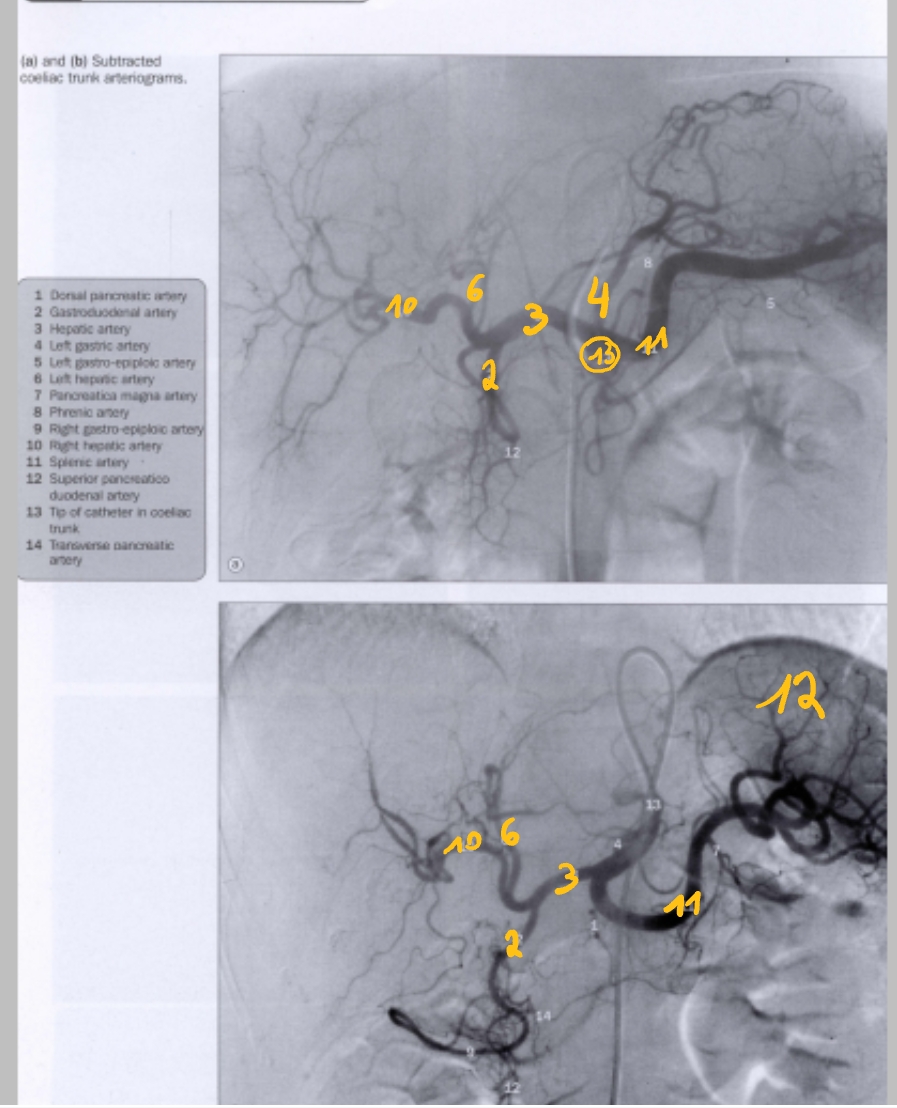

(catheter via a. femoralis → a. iliaca externus → a. iliaca communis → aorta abdominalis → truncus coeliacus)

a. gastroduodenalis

a. hepatica communis

a. gastrica sinistra

a. hepatica sinistra

a. hepatica dextra

a. splenica

milt

truncus coeliacus